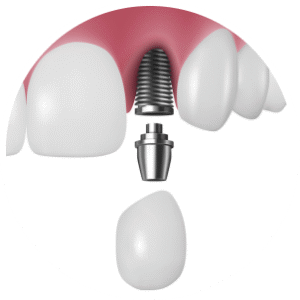

即時インプラント(最新のルートメンブレンテクニック)

即時入れ歯(インプラントを支えに入れ歯を即時で固定する治療法)